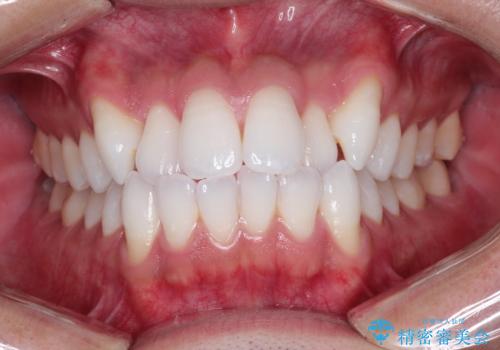

前歯の突出を防ぎながらガタつきを解消。上下左右4番抜歯による審美ワイヤー矯正

担当医 河口智英